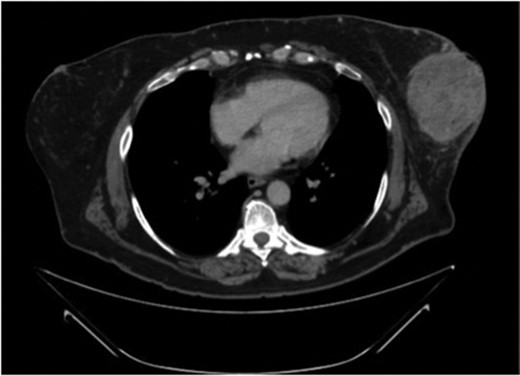

Physical exam revealed a large fungating mass extruding from the left breast at the 3 o'clock position with overlying ulceration and cellulitic changes to the surrounding skin (Fig. 1). CT scan of the chest demonstrated a 9.2 × 8.6 cm heterogeneous mass in the left breast with reactive lymphadenopathy up to 3.1 cm in the ipsilateral axilla (Fig. 2). There were no suspicious findings in the right breast on CT and mammographic imaging (Fig. 3). MRI of the brain demonstrated no evidence of metastatic disease. Core needle biopsy (CNB) of the mass demonstrated focal granulomatous reaction with foreign body giant cells. CNB of the enlarged axillary node was benign.

CT scan of the chest demonstrates a 9.2 × 8.6 cm mass within the left breast causing ulceration of the overlying skin.